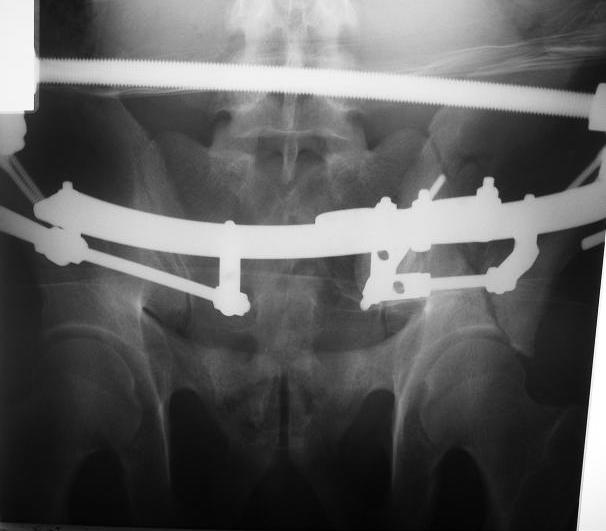

Поступил пациент после кататравмы (упал с высоты 4м). После обследования установлен Ds: Сочетанная травма. ЗТГК перелом 5-6 ребер справа. Ушиб левого леогкого. Оскольчатый перелом крыла подвздошной кости слева, со смещением. в экстренном порядке выполнена операция о/синтез таза стержневым аппаратом. Снимки прилагаются. Пациент со 2-го дня стал ходить без костылей. Из анамнеза жизни у пациента имеется гепатит В и С, с 1998г. употребляет наркотики (героин 1г в день нормальная доза). На контрольных снимках таза в аппарате смещение отломков сохраняется, да еще и стержни сломались. Подскажите ув.коллеги, как поступить в данной ситуации: оставить все как есть или добиваться репозиции в аппарате, или планировать на открытую репозицию. На сегодняшний день пациент стабилен, по анализам компенсирован. Принимает героин по другому справиться не может. С ув. Андрей

C момента травмы прошло ровно 10 дней. Да Максим, вы как в воду глядели, у стержней появились признаки воспаления. Аппарат демонтирую.

Алексей Владимирович, спасибо за конкретные варианты лечения, все взвешу и какой то вариант применю. В данном случае случае не было необходимости в экстренном аппаратном лечении наверно. К сожалению не сразу оценил возможности аппарата при данном переломе. Спасибо за советы всем!!!